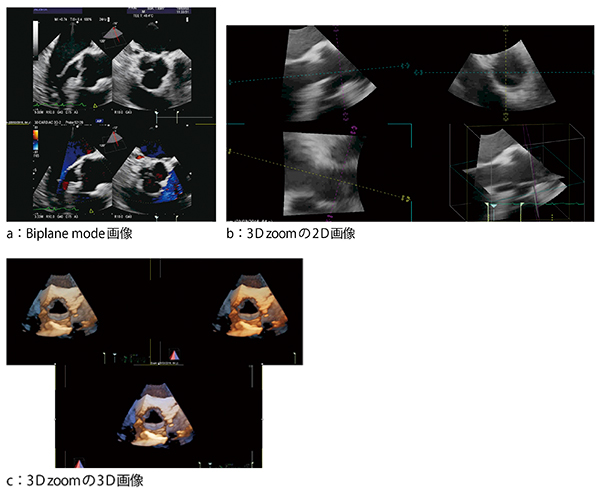

大動脈弁のBiplane modeの画像(図2 a),および3D zoomの2D画像(図2 b)と3D画像(図2 c)を示す。図2 cは大動脈弁を大動脈側から見ており,左冠動脈,左冠尖,右冠尖,無冠尖が確認できる。

図2 大動脈弁の3D TEE画像